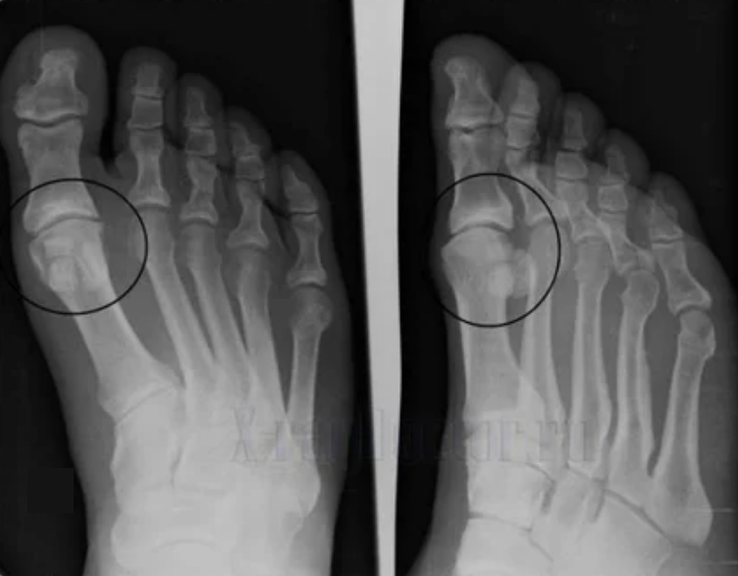

Para hacer un diagnóstico, los reumatólogos estudian las quejas del paciente y prescriben un examen X -Ray. La mayoría de las veces, la radiografía se usa en 2 proyecciones. El médico analiza la presencia de trastornos distróficos en el cartílago hialino y las articulaciones óseas. Si se reduce la brecha articular, los huesos se deforman o se aplanan, hay formaciones quísticas en la superficie del cartílago, los osteofitos son signos obvios de artrosis. Durante la inspección, la artrosis indica la inestabilidad de la articulación: el eje de las extremidades y la subluxación se altera.

A menudo, una imagen de rayos x no puede dar información completa sobre la condición de la articulación. Para un estudio más exhaustivo, se prescribe la tomografía computarizada, es efectivo para examinar los huesos. La resonancia magnética se usa con mayor frecuencia para estudiar tejidos blandos.